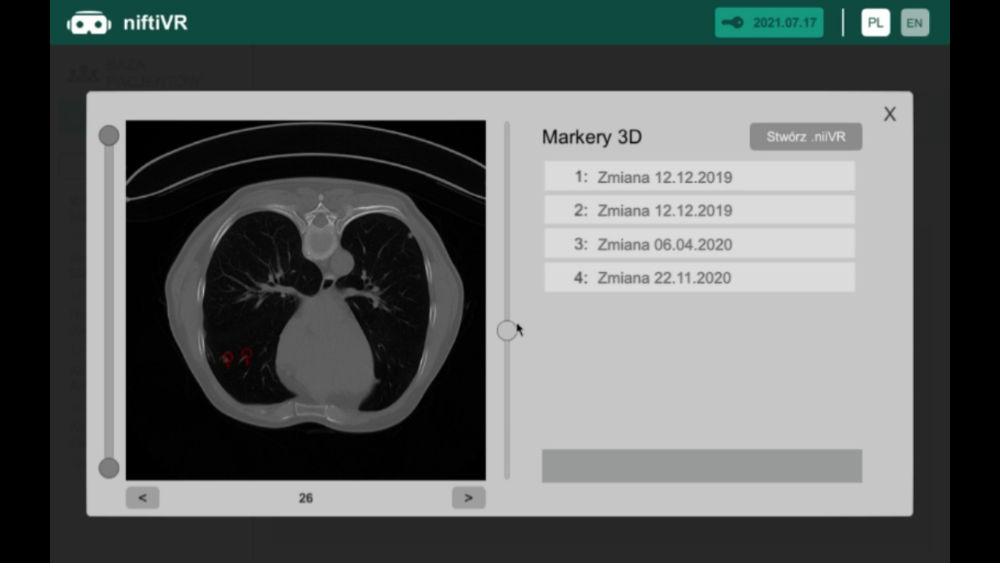

Preview of CT images from

brand new perspective

Profesional tool for doctors witch allowing analizing rentgen image analizing in VR

A modern program for analizing images from the tomograph

Thanks to our program, you will be able to manage lists of your patients in a quick and organized manner, saving time and more efficiently analyzing images from a computer tomograph or magnetic resonance imaging. The application allows you to load photos into the Virtual Reality environment, giving you the opportunity to view and analyze them in a new, unconventional way. Photos displayed in the form of 3D models can be freely rotated and viewed from different angles.